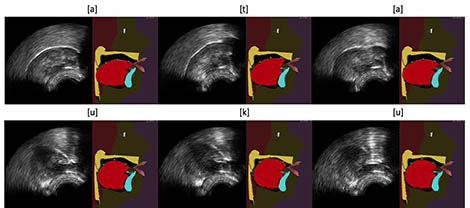

Exemple d'animations du modèle de langue de la tête parlante articulatoire du GIPSA-lab à partir d'images échographiques, à l'aide de l'algorithme « Integrated Cascaded Gaussian Mixture Regression » pour les séquences [ata] (haut) et [uku] (bas).

Depuis quelques années, des chercheurs anglo-saxons semblent privilégier la technique de l'échographie pour la conception de ces systèmes de retour visuel. L'image de la langue est alors obtenue en plaçant sous la mâchoire d'un locuteur une sonde analogue à celle classiquement utilisée pour l'imagerie du cœur ou du fœtus. Cette image est parfois jugée difficile à exploiter par le patient car elle n'est pas de très bonne qualité et ne donne aucune information sur la place du palais et des dents. Dans ces nouveaux travaux, les chercheurs français proposent d'améliorer ce retour visuel en animant automatiquement et en temps réel une tête parlante articulatoire à partir des images échographiques. Ce clone virtuel d'un véritable locuteur, en développement depuis de nombreuses années au GIPSA-lab, permet une visualisation plus intuitive, car contextualisée, des mouvements articulatoires.

La force de ce nouveau système repose sur un algorithme d'apprentissage automatique (machine learning), sur lequel les chercheurs travaillent depuis plusieurs années. Cet algorithme permet (dans une certaine limite) de traiter des mouvements articulatoires que l'utilisateur ne maîtrise pas encore lorsqu'il commence à utiliser le système. Cette propriété est indispensable pour les applications thérapeutiques visées. Pour atteindre une telle performance, l'algorithme exploite un modèle probabiliste construit à partir d'une grande base de données articulatoires acquises sur un locuteur dit "expert", capable de prononcer l'ensemble des sons d'une ou plusieurs langues. Ce modèle est adapté automatiquement à la morphologie de chaque nouvel utilisateur, lors d'une courte phase d'étalonnage du système, au cours de laquelle le patient doit prononcer quelques phrases.